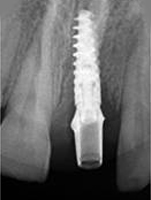

X-ray of Implant

Placement of Bone Grafting

X-ray of Implant + Abutment

X-ray of Implant +

Abutment+ Prosthesis